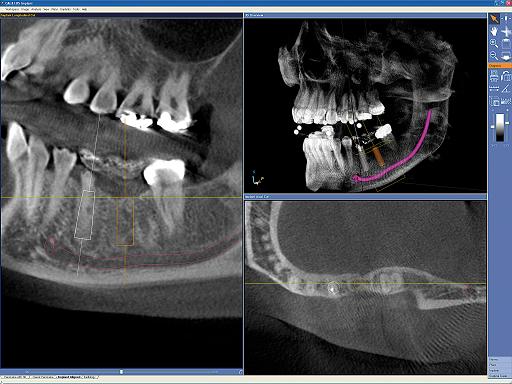

- Программа, выводящая привычные стоматологам панорамные снимки с интуитивным трехмерным управлением объемом и абсолютно новыми возможностями диагностики.

Совершенная диагностика с GALILEOS и GALAXIS

После прохождения короткой реконструкции GALILEOS показывает не только 3D-изображения отличного качества. Большой объем с высоким разрешением деталей отображается при панорамной, цефалометрической и TSA-съемке. Привычный панорамный снимок позволяет интуитивно ставить диагноз в масштабе реального времени.

Новая, интегрированная в SIDEXIS XG программа GALAXIS уверенно ведет пользователя в будущее диагностики.

Надежная 3D-диагностика

В 3D-объеме GALILEOS (15х15х15) см3 на панорамном и цефалометрическом снимке можно интуитивно переходить из одного окна в другое и обследовать различные зоны.

- Программа GALILEOS Implant (1 плавающая лицензия).